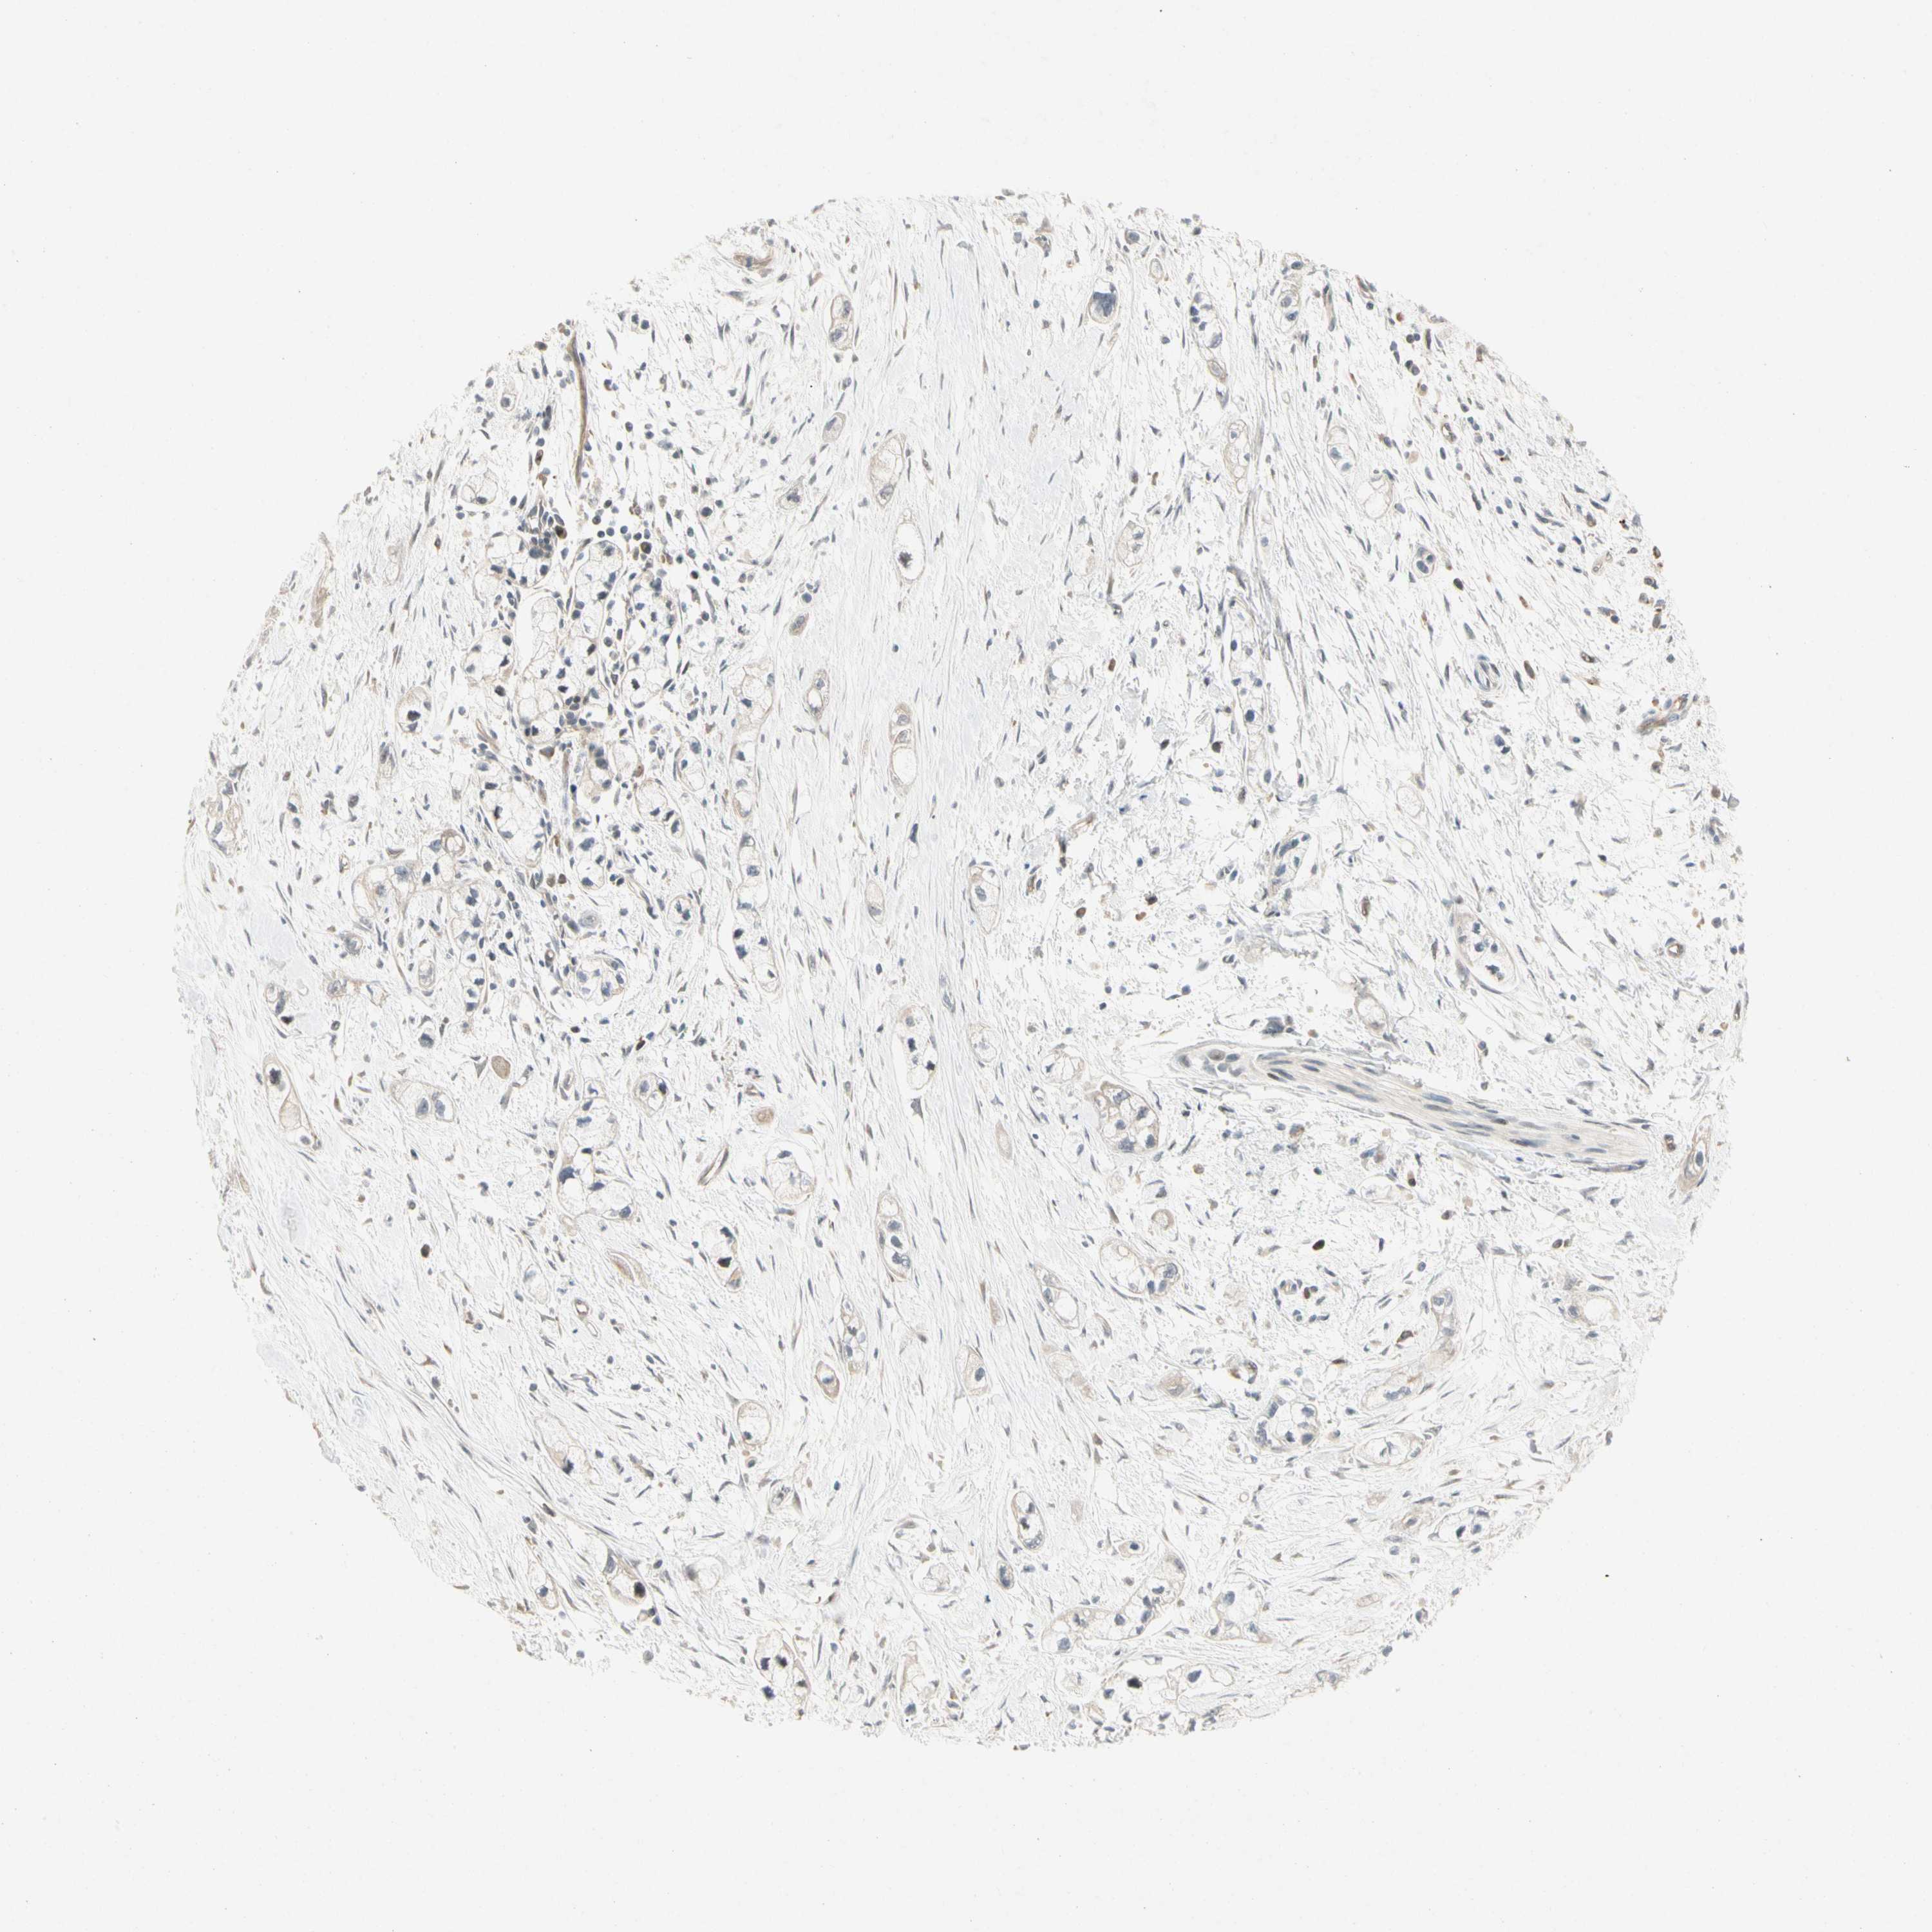

PANCREATIC CANCER - Protein expressioni

A mouse-over function shows sample information and annotation data. Click on an image to view it in a full screen mode. Samples can be filtered based on level of antibody staining by selecting one or several of the following categories: high, medium, low and not detected. The assay and annotation is described here.

Note that samples used for immunohistochemistry by the Human Protein Atlas do not correspond to samples in the TCGA dataset.

Antibody stainingi

Antibody staining in the annotated cell types in the current human tissue is reported as not detected, low, medium, or high, based on conventional immunohistochemistry profiling in selected tissues. This score is based on the combination of the staining intensity and fraction of stained cells.

Each image is clickable and will lead to virtual microscopy that enables deeper exploration of all samples and also displays staining intensity scores, fraction scores and subcellular localization as well as patient and tissue information for each sample.

Antibody HPA007859

Staining

High

Medium

Low

Not detected

Intensity

Strong

Moderate

Weak

Negative

Quantity

>75%

75%-25%

<25%

None

Location

Nuclear

Cytoplasmic/membranous

Cytoplasmic/membranous,nuclear

Adenocarcinoma, NOS